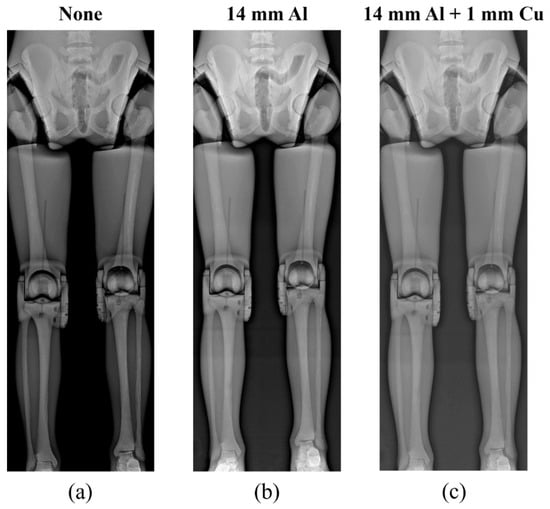

Figure 6, Figure 7 and Figure 8 show the acquired whole-spine AP, LAT, and long-leg AP X-ray images with and without additional filters, respectively. Visual evaluation of the obtained images confirmed that the image quality was improved when an additional filter based on Al and Cu materials manufactured with a 3D printer was used in thin areas such as the C-spine and ankle. In particular, the highest quality was observed in all the acquired X-ray images when a filter combining 14 mm thick Al + 1 mm thick Cu was used.

Figure 8.

Acquired long-leg AP X-ray images without and with additional filters. (a) Long-leg AP image (a) without an additional filter, (b) with a 14 mm thick Al additional filter, and (c) with a 14 mm thick Al + 1 mm thick Cu composite additional filter.